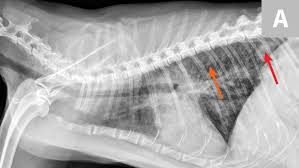

Diagnosis Lungworm Infection Catwatch Newsletter

Diagnosis Lungworm Infection Catwatch Newsletter from s30379.pcdn.co